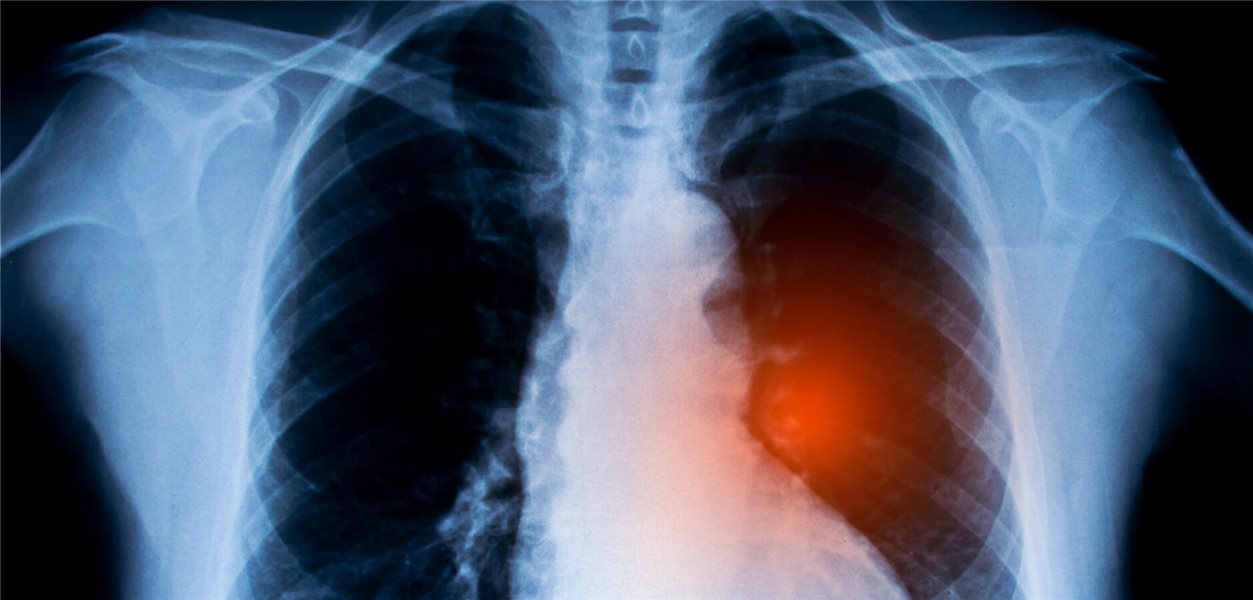

Nicht-kleinzelliges Lungenkarzinom: Krebsimpfstoffe könnten Überlebenschancen erhöhen

Für Menschen mit fortgeschrittenem nicht-kleinzelligem Lungenkarzinom kommen nach der Erstlinientherapie auch Krebsimpfstoffe in Frage. In einer Metaanalyse wurde deren klinische Wirksamkeit untersucht. Besonders eine Patientengruppe schien zu profitieren.